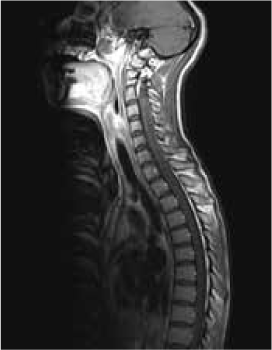

Magnetic resonance imaging (MRI) of the brain showed symmetrically increased T2-weighted and fluid-attenuated inversion recovery signal in the central pons (Figure 1) and in the striatum of the basal ganglia (Figure 2), with no contrast enhancement seen on corresponding T1-weighted postgadolinium images (Figures 3 and 4). Spinal MRI (Figure 5) demonstrated high signal on T2-weighted images from the area postrema in the medulla extending caudally to the T9 thoracic segment, with marked cord swelling and mild enhancement on T1-weighted postcontrast studies (Figure 6), in keeping with a longitudinally extensive inflammatory myelitis.

Magnetic resonance image of spine shows longitudinally extensive intrinsic increased cord signal on sagittal T2-weighted sequences

Magnetic resonance imaging shows longitudinally extensive cord signal abnormality with peripheral enhancement on sagittal T1-weighted postcontrast sequence